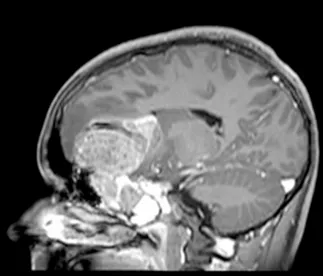

一名15岁、既往健康的男性,因额部头痛加剧、恶心、呕吐和疲劳两周病史就诊。家属注意到在就诊前一个月出现言语失控和非典型行为。他的神经系统检查显示双侧视乳头水肿,无其他局灶性缺损。所有血液检查均正常,血清生殖细胞肿瘤标志物也为阴性。脑和鼻旁窦的计算机断层扫描(CT)和磁共振成像(MRI)扫描显示,右侧有一个5.5 x 4.4 x 5.6厘米的肿块,起源于鼻腔、筛窦和蝶窦。它已侵蚀筛板进入前颅窝。该肿块在CT扫描上未钙化(图1),与脑组织等密度,伴有不均匀的对比增强。该肿块在T1和T2加权MR图像上(图2、3、4)与脑组织等信号,并在钆增强后显示不均匀强化。注意到周围有血管源性脑水肿和占位效应。脊柱MRI未见转移证据。

图3:矢状位T1加权钆增强MRI扫描,显示肿瘤团块从鼻旁窦侵蚀进入前颅窝。